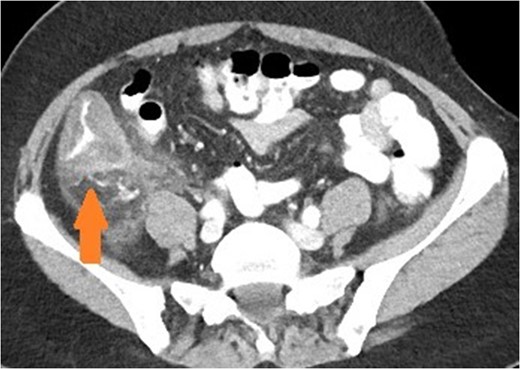

Axial view of patient with appendicitis. Eccentric caecal wall thickening (maximal surrounding the appendiceal orifice) with layered mural contrast enhancement secondary to prominent submucosal oedema (arrow) and prominent pericolic fat stranding represent the CT manifestation of the surgical phlegmon.